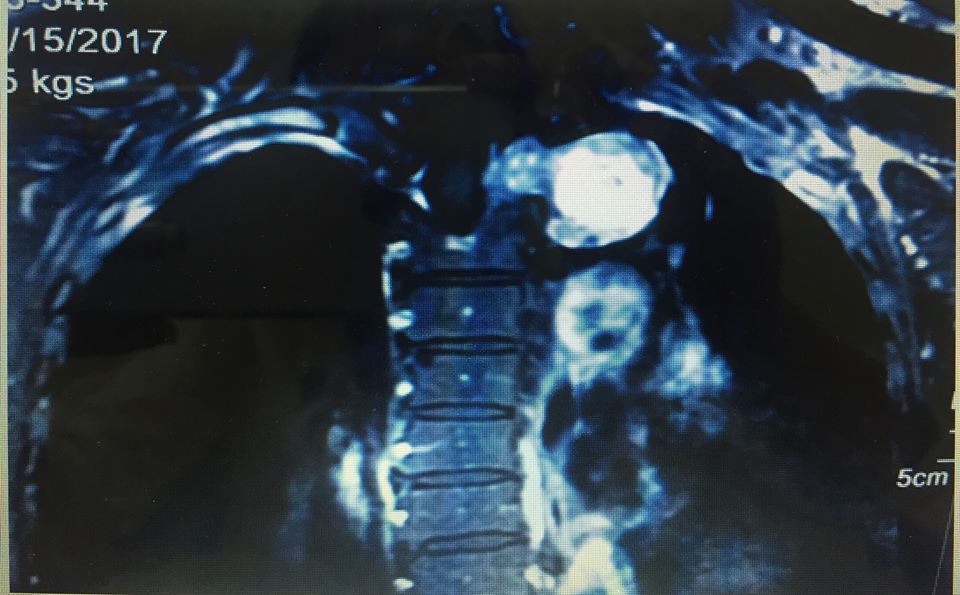

Khối u "quả tạ" trong lồng ngực bệnh nhân Y. (Ảnh BSCC)

Bệnh nhân Hứa Thị Y., 61 tuổi, nhập viện trong tình trạng tức ngực kéo dài, đau lưng và vai tay trong gần một năm. Hóa ra, bệnh nhân có khối u hình ... quả tạ. Bệnh viện K Trung ương vừa phẫu thuật thành công cho bệnh nhân nữ 61 tuổi này.

Trước đó, bệnh nhân Hứa Thị Y., 61 tuổi, nhập viện trong tình trạng tức ngực kéo dài, đau lưng và vai tay trong gần một năm, đã điều trị nhiều nơi nhưng không hiệu quả. Bệnh nhân đến khám tại Bệnh viện K Trung ương, được chẩn đoán là u thần kinh tủy sống, chỉ định phẫu thuật loại bỏ khối u nhằm giải phóng chèn ép tủy và chèn ép khoang trung thất.

Sau khi hội chẩn, các chuyên gia ung bướu trong bệnh viện, các bác sĩ nhận định đây là ca mổ phức tạp vì khối u hình quả tạ vừa nằm trong ống tủy ngực vừa nằm trong lồng ngực liên quan đến nhiều chức năng quan trọng như: vận động, cảm giác, phổi, buồng tim, các tĩnh mạch và động mạch lớn xuất phát từ tim.